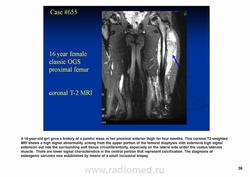

Рентгенологически выявляют в очаге деструкции участки обызвествления в виде крапчатости; кортикальный слой с признаками эрозии со стороны эндоста и истончения; размеры опухоли более 4 см; периостальная реакция слабо выражена или отсутствует; может наблюдаться деструкция кортикальной кости и наличие мягкотканного компонента; в длинных костях локализуется чаще в метафизах и диафизах; интенсивное внутрикостномозговое распространение.